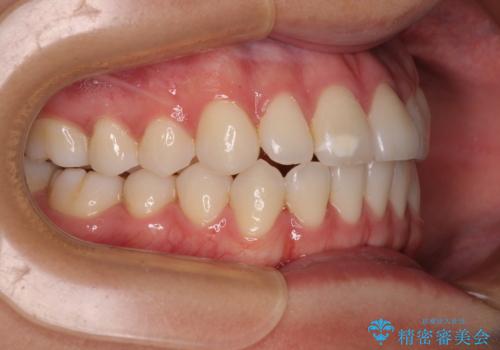

- 前歯のデコボコと奥歯の咬み合わせを気にして来院された患者様です。

右側の奥歯は、上が外側に転位した鋏状咬合を呈しており、前歯のデコボコ改善と並行して咬み合わせを改善していく必要がありました。

ワイヤー装置でもマウスピースでも、どちらでも適用の症例でしたが、片側の鋏状咬合はマウスピース矯正ではしっかりと改善できる可能性が低いことや、何と言っても自己管理の煩わしさがないことから、ワイヤー装置を選択されました。